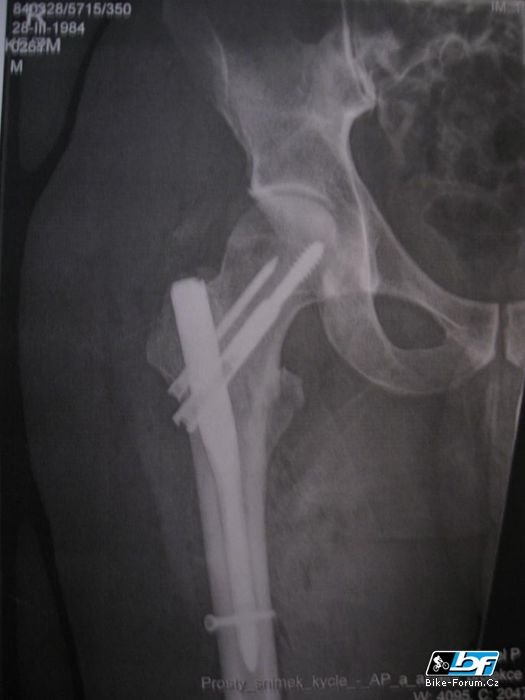

tak jsem blbě spad s kola a udělalo se bebi :o)

Mám stejné, jen ten implantát ve stehení kosti mám až ke kolenu. Přeju co nejrychlejší rehabilitaci a dobré zhojení !!